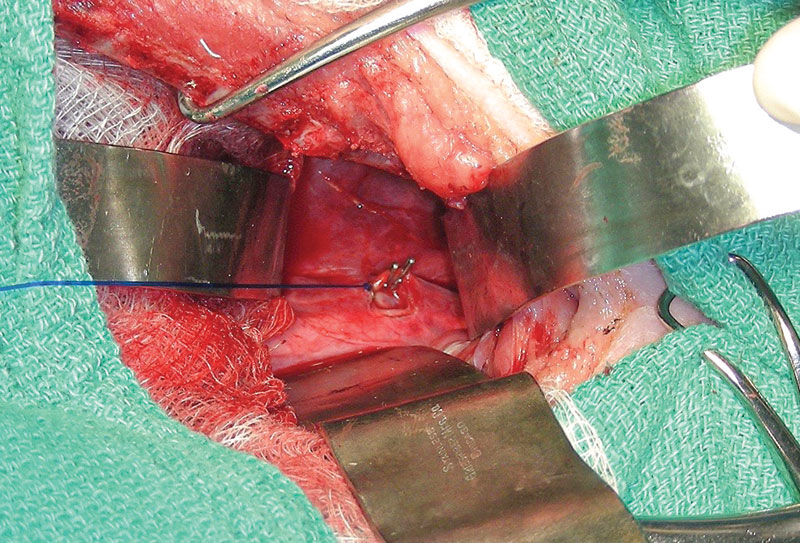

Surgical outcome for chylothorax in small animal patients is highly variable, with the prognosis more guarded in cats than in dogs.1,13 Traditional surgical interventions for idiopathic chylothorax are highly invasive, typically requiring open chest surgery (Figures 1 and 2) with the possibility of added abdominal laparotomy.3,4 Owners may be averse to such highly invasive procedures, with a possibility of nonresolution or continued need for pleural effusion evacuation. The use of minimally invasive surgery in small animals has made advances in the last several decades, and its use has been applied for surgical conditions, such as chylothorax.13-15

Figure 1. Thoracic duct ligation in a cat using the traditional intercostal thoracotomy approach. Photo courtesy Dr. Eric Monnet.

Figure 2. Subtotal pericardiectomy in a cat via median sternotomy. Also shown is the transthoracic omentalization. Photo courtesy Dr. Eric Monnet